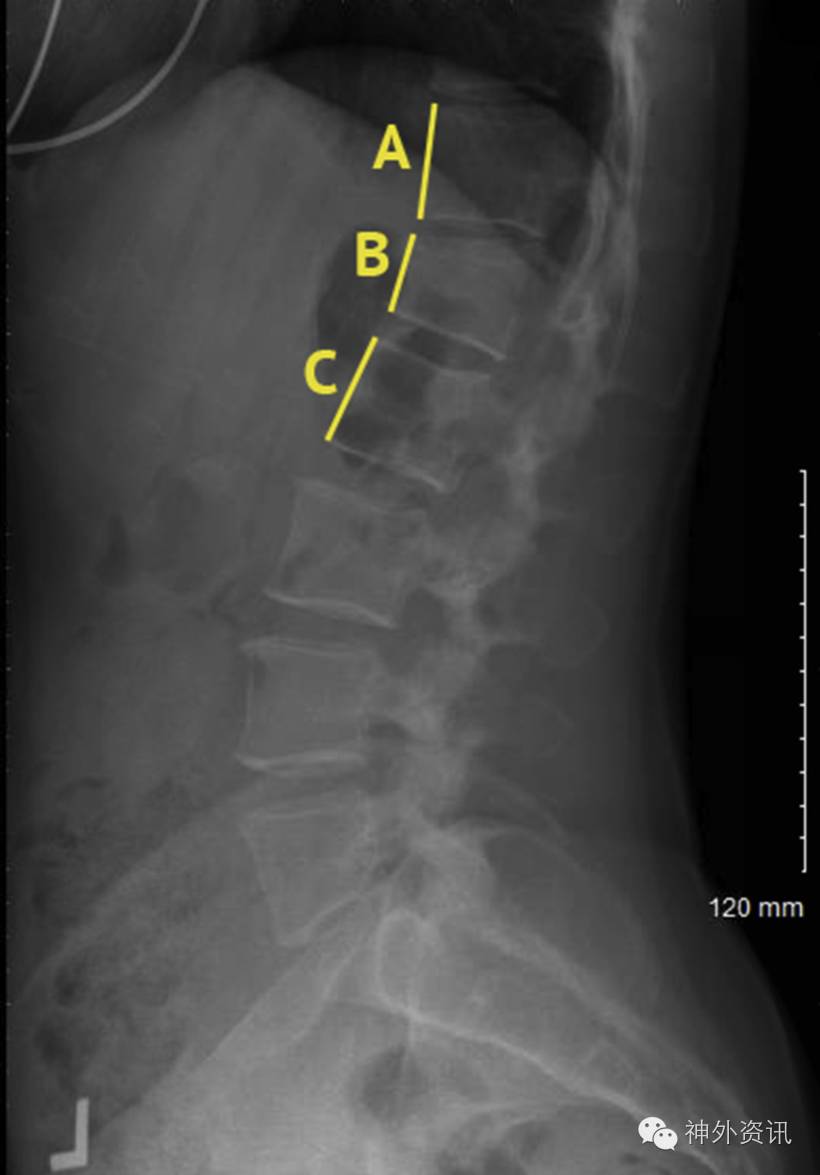

图1. L1椎体压缩性骨折X线片。上图显示不包括皮质边缘的平均CT值测量方式。

图2. L1椎体压缩性骨折的压缩百分数=2B/(A+C)×100%